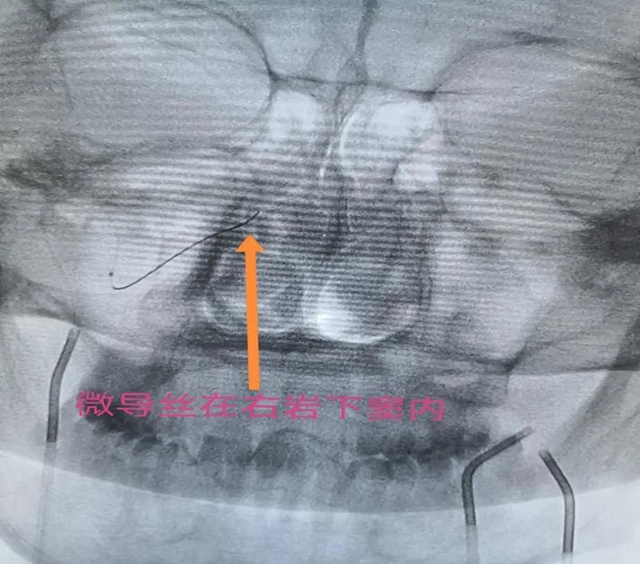

“这项技术需要采血的脑部血管非常细微,对神经介入技术要求很高,但此处采血,最能反应病人实际水平,对定位定性诊断和精准治疗有非常高的临床价值。”黄昌仁教授表示,通过多学科合作完成的这项技术,填补了神经外科神经介入的一项空白,更是多学科联合诊疗的成功范例。

最终,历时两个多小时,采血成功完成。根据取血结果,唐先生确诊患库欣病,再通过比较左右岩下窦静脉的激素含量,为指导后续手术进行精准诊断和治疗提供了依据。